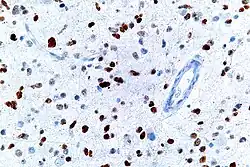

This image shows different patterns of p53 expression in endometrial cancers on chromogenic immunohistochemistry, whereof all except wild-type are variably termed abnormal/aberrant/mutation-type and are strongly predictive of an underlying TP53 mutation:[92]